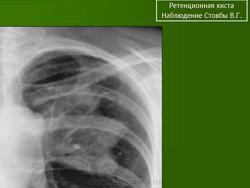

Ретенционная киста. Чт, 11/08/2011 - 20:34 #1 Nikolas Не на сайте Был на сайте: 1 месяц 1 неделя назад Зарегистрирован: 21.12.2010 - 20:37 Публикации: 4560 бронхиальной кисты не наблюдал. Спасибо за наблюдение. С уважением Nikolas Пт, 13/04/2018 - 22:06 #2 Миргалина Не на сайте Был на сайте: 1 месяц 5 дней назад Зарегистрирован: 06.08.2015 - 20:04 Публикации: 2882 Nikolas wrote: бронхиальной кисты не наблюдал. Спасибо за наблюдение. С уважением Nikolas Really? А какие Вы наблюдали?